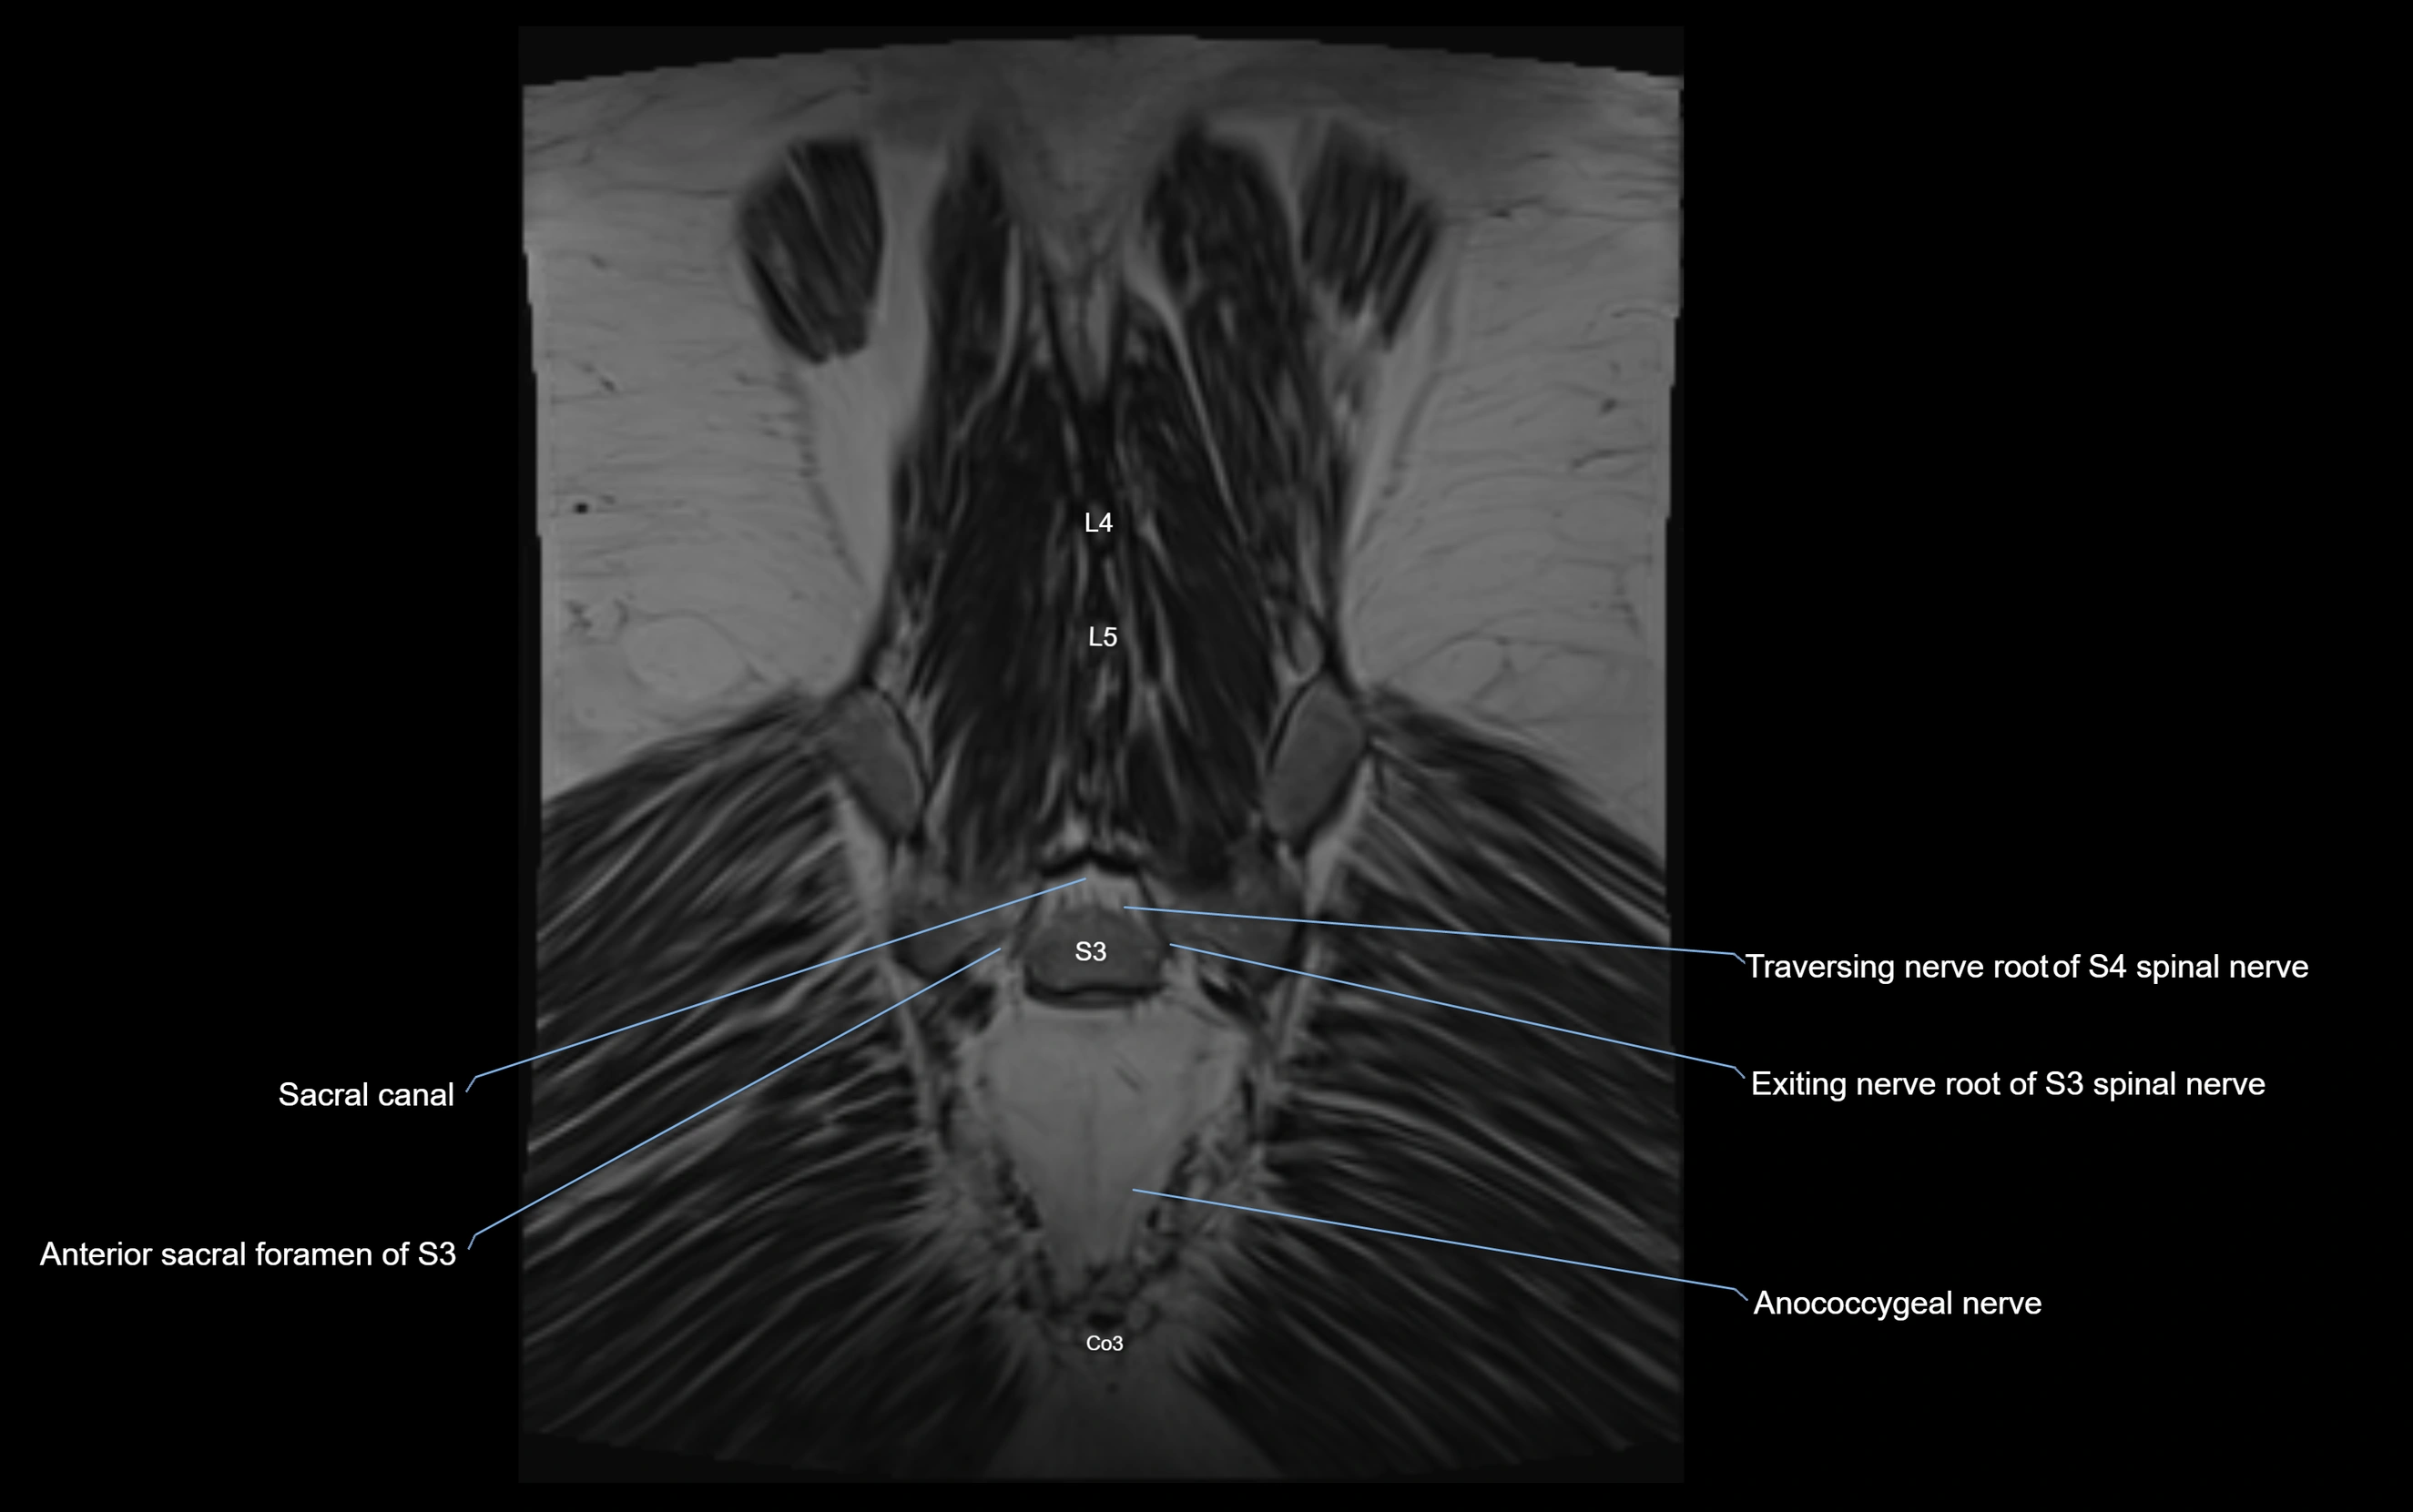

MRI image

image